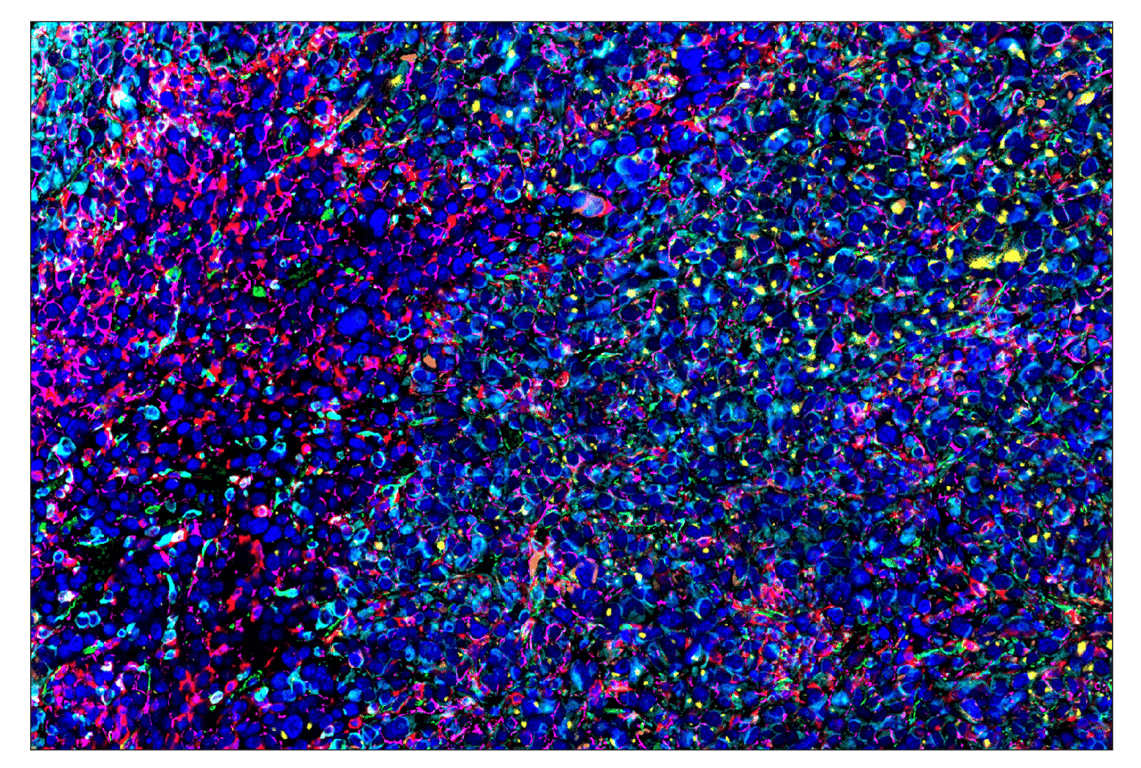

SignalStar™ multiplex immunohistochemical analysis of paraffin-embedded human gastric adenocarcinoma using α-Smooth Muscle Actin (D4K9N) & CO-0024-750 SignalStar™ Oligo-Antibody Pair #29280 (cyan), CD31 (PECAM-1) (89C2) & CO-0028-488 SignalStar™ Oligo-Antibody Pair #83823 (green), CD68 (D4B9C) & CO-0007-594 SignalStar™ Oligo-Antibody Pair #77318 (yellow), and Pan-Keratin (C11) & CO-0003-647 SignalStar™ Oligo-Antibody Pair #16373 (red). All fluorophores have been assigned a pseudocolor, as indicated. Staining was performed on the BOND RX by Leica Biosystems.

Immunohistochemistry Image 1: alpha-Smooth Muscle Actin (D4K9N) & CO-0024-488 SignalStar<sup>™</sup> Oligo-Antibody Pair